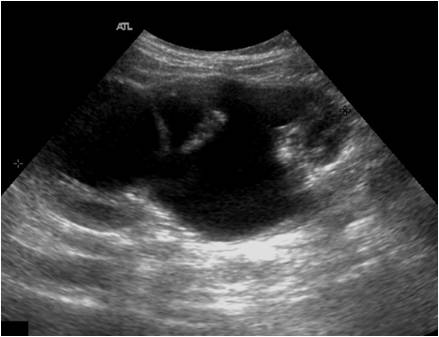

Donde encontramos un «pelvis extrarrenal», anecoica, grande en la salida del riñón hacia el Uréter…El parénquima renal está prácticamente conservado, casi normal o normal…Pero en extremos graves, como la hidronefrosis de III-IV grado encontramos estas imágenes:

Where we find an «extrarenal pelvis», anechoic, large at the exit of the kidney to the ureter … The renal parenchyma is practically preserved, almost normal or normal … But in severe extremes, such as hydronephrosis of III-IV degree we find these images:

Observad que aquí el Riñón está «colapsado» por una importante cantidad de líquido dentro del órgano, lógicamente es anecoico y el parénquima renal puede verse afectado, disminuido al punto que si no se actúa el riñón podría sufrir daños en su función…

Observe that here the Kidney is «collapsed» by a significant amount of fluid inside the organ, logically it is anechoic and the renal parenchyma can be affected, diminished to the point that if the kidney is not acted it could suffer damages in its function … Sometimes I can find another pathological figure that we will study in its particular micropost, the Megauréter. Between these two extremes we can find quantity of images that must be interpreted and classified by the radiologists.